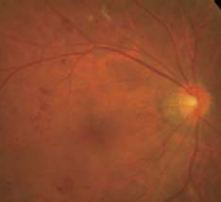

正常视网膜血管

正常眼底造影